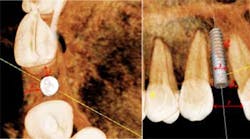

The orthodontist and the surgeon must also take into account the space appropriation in the interradicular area as well. The minimum spacing between the roots is generally 5 mm. This amount of space will allow the implant to be surrounded by 0.75 mm and 1.0 mm of bone, which is sufficient to support normal functional loading and ensure good long-term osseointegration. (22) During the space opening aspect of orthodontic care, the orthodontist must make a compensating bend to diverge the roots, especially when canines are initially distal angulated, since the canine root apex inevitably lags behind the crown when distalized. The orthodontist also has to pay particular attention to the skeletal relationship of the patient in these cases because in an Angle Class III tendency type case, the maxilla is narrow and the crowns tend to be tipped labially, which in turn results in adequate space for the restoration but insufficient space at the apex for fixture placement and may necessitate an alternative type of restoration or a shorter implant fixture. (3,6)

In any case, but especially Angle Class III cases, it is good practice for the restorative dentist or surgeon to take a periapical radiograph prior to the removal of the orthodontic appliances to ensure that adequate interradicular space has been established. Once the root position has been confirmed and appliances are removed, it becomes especially important to establish a retention protocol that will prevent relapse of the root position. Removable appliances are adequate to maintain the interradicular spacing in the short-term, but many times these cases need to be retained for a number of years until growth is complete and a more long-term provisional is recommended. In cases with a high relapse potential, a resin-bonded fixed partial denture should be considered. This type of restoration has the advantage of being esthetic, conservative, and eliminates compliance issues, all while maintaining the established tooth positions and site development.

and a narrow maxilla limits the orthodontist’s ability to torque the

roots and creates a convergence of the roots, which limits the

apical interradicular space for implant placement.